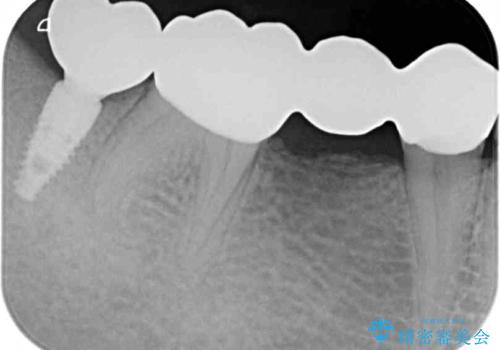

抜歯してからインプラント埋入までには時間がかかるため、その間に下顎左右臼歯の金属のブリッジをオールセラミックへ変えていくこととしました。

目立つ部分の銀歯や気になる変色歯をまとめてきれいに仕上げることができました。